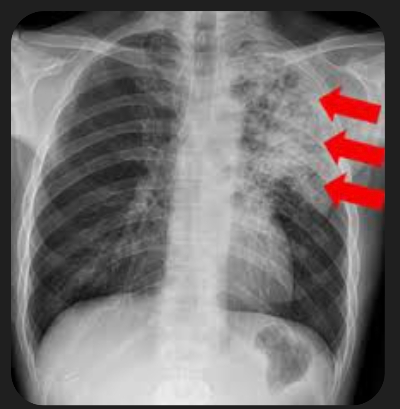

5. 폐렴 증상

폐렴 증상은 질환이 진행되면서 다양하고 심각하게 나타납니다. 주요 증상으로는 고열, 후두통, 가래를 동반한 강한 기침, 흉통, 호흡곤란, 빠른 호흡 등이 있습니다. 가래는 화농성으로 노란색이나 녹색을 띕니다.

바이러스성 폐렴은 세균성 폐렴에 비해 천천히 진행되는 경향이 있으며, 호흡 시 쌕쌕거리는 소리가 나거나 숨을 쉬기 어려운 증상이 나타날 수 있습니다.